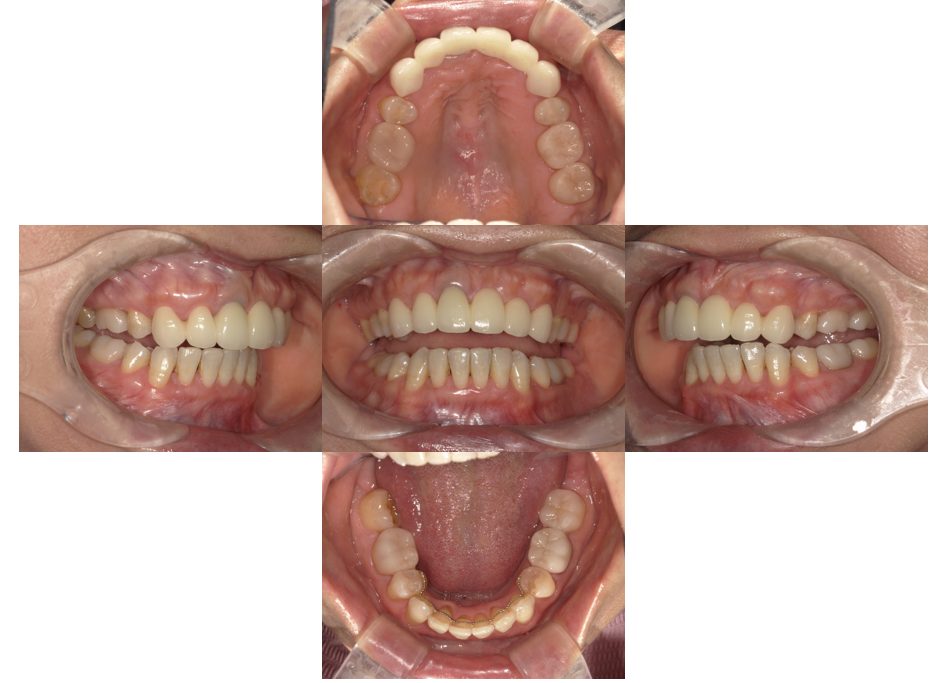

矯正治療・根管治療・補綴治療の症例紹介(三隅歯科クリニック)

三隅 賢祐(三隅歯科クリニック)

症例詳細

| 主訴 | 過去作成した右下の被せ物がずれて入っており、たまに腫れる。歯並びも気になる。 |

| 治療内容 | 矯正治療を行いました。 |

| 治療費 | 800,000円(税込み) |

| 治療期間 | 2年半(矯正治療期間 2年) |

| 治療回数 | 30回 |

| 想定されたリスク | 術前に基礎資料を整え分析し、セットアップモデル等でシミュレーションをしておかないと、予定通りの治療が行えないリスクがあった。 |